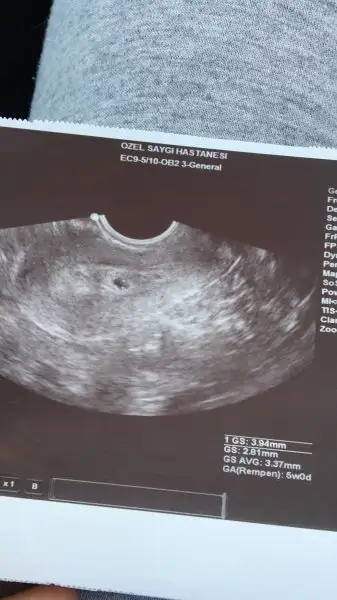

Canım endişelenme 7 haftalıkken vajinal muayeneyle görebildi doktorMrb kızlar beni bi korku sardı yaa

Dr perşembe günü karından bakmisti 6.haftamda keseyi gorebildim sadece sizce normal mi bu sizde karından mi bakilmistiniz birde bebeği kaçıncı haftada görebildiniz

Alttan baksa gorebilirmiydim acaba diyorum

Normal demek ki o zaman canım sağol rahatladım biraz şimdi .kalp atışını bile duyanlar var o yüzden endiselendim bendeCanım endişelenme 7 haftalıkken vajinal muayeneyle görebildi doktor